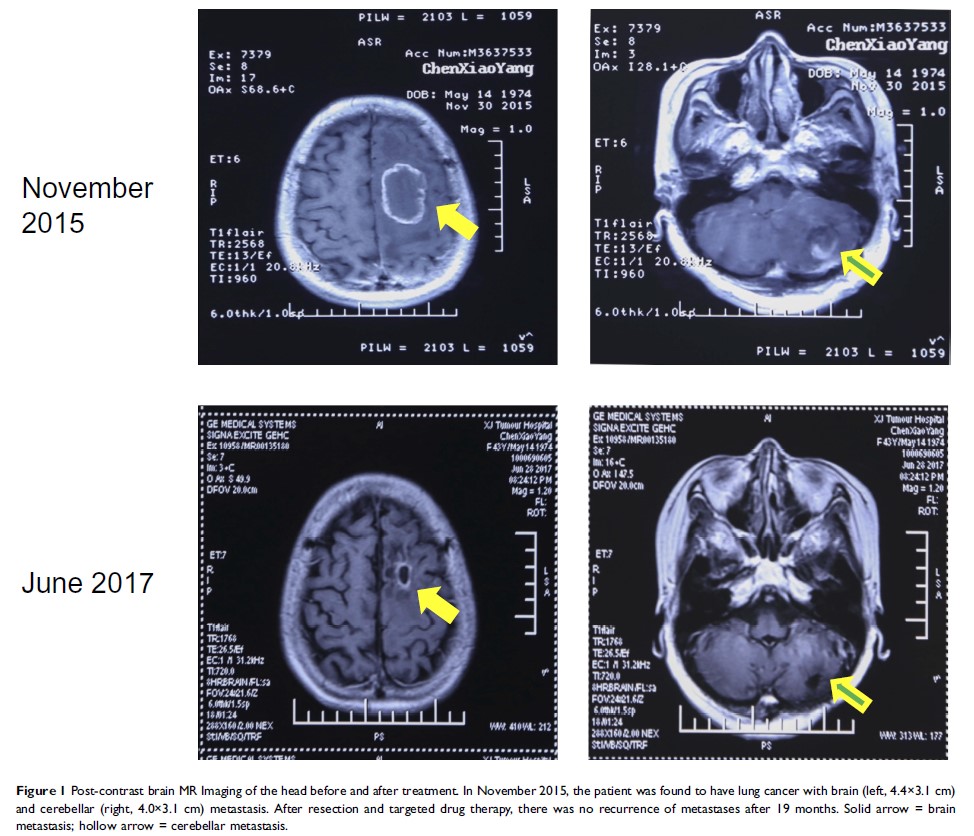

Case Report

非小细胞肺癌患者氢气治疗后脑转移完全消失:个案报道